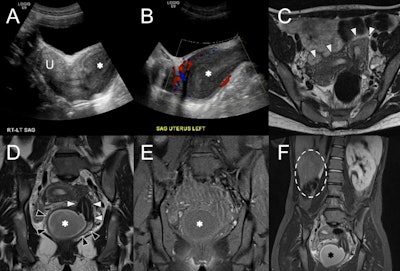

Cystic/necrotic pelvic mass mimicking hydro/hematometra in a 65-year-old female with recurrent ovarian cancer post total abdominal hysterectomy and bilateral salpingo-oophorectomy. Sagittal (A) and coronal (B) contrast-enhanced CT images demonstrate a soft tissue mass (white arrowheads) with central hypodensity, suggestive of cystic/necrotic component (asterisk). The mass is inseparable from the vaginal cuff (V) and mimics an obstructed, retroverted uterus, but instead represents local recurrence post hysterectomy.

Nonuterine masses such as nonuterine neoplasms and cystic lesions may mimic reproductive tract obstruction, and this is especially true if lesions are large, making localization challenging.

“Following ultrasonographic assessment, CT and MRI can be used to assist in characterization and localization. The vascular supply may assist in localization, for example, vascular supply from the gonadal vessels may suggest ovarian origin,” they said.